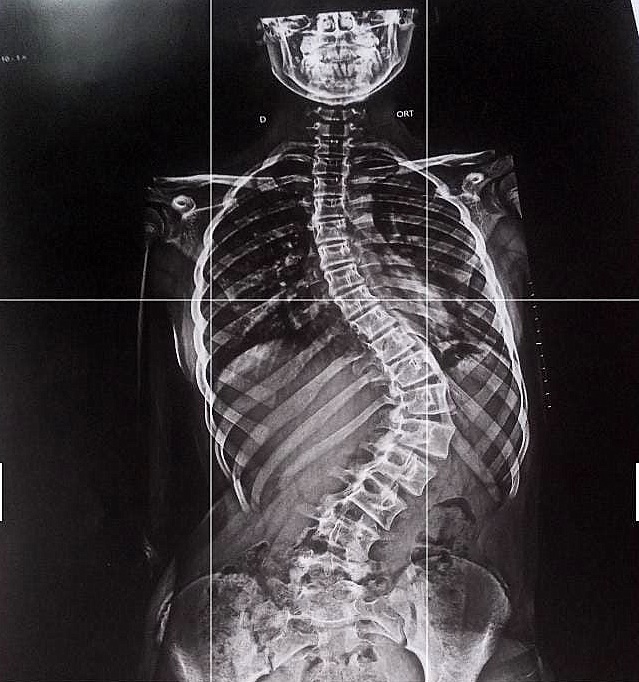

Agatha Rebeca, de 12 anos, foi diagnosticada com um grave problema na coluna.

Agatha Rebeca Maestrello foi diagnosticada com Escoliose Idiopática.

Sua mãe explica que a própria medicina não consegue explicar da onde veio o problema, isto é, não se trata de problema de postura ou nem genética "foi de repente. O médico também disse que nem fisioterapia resolve”, observou.